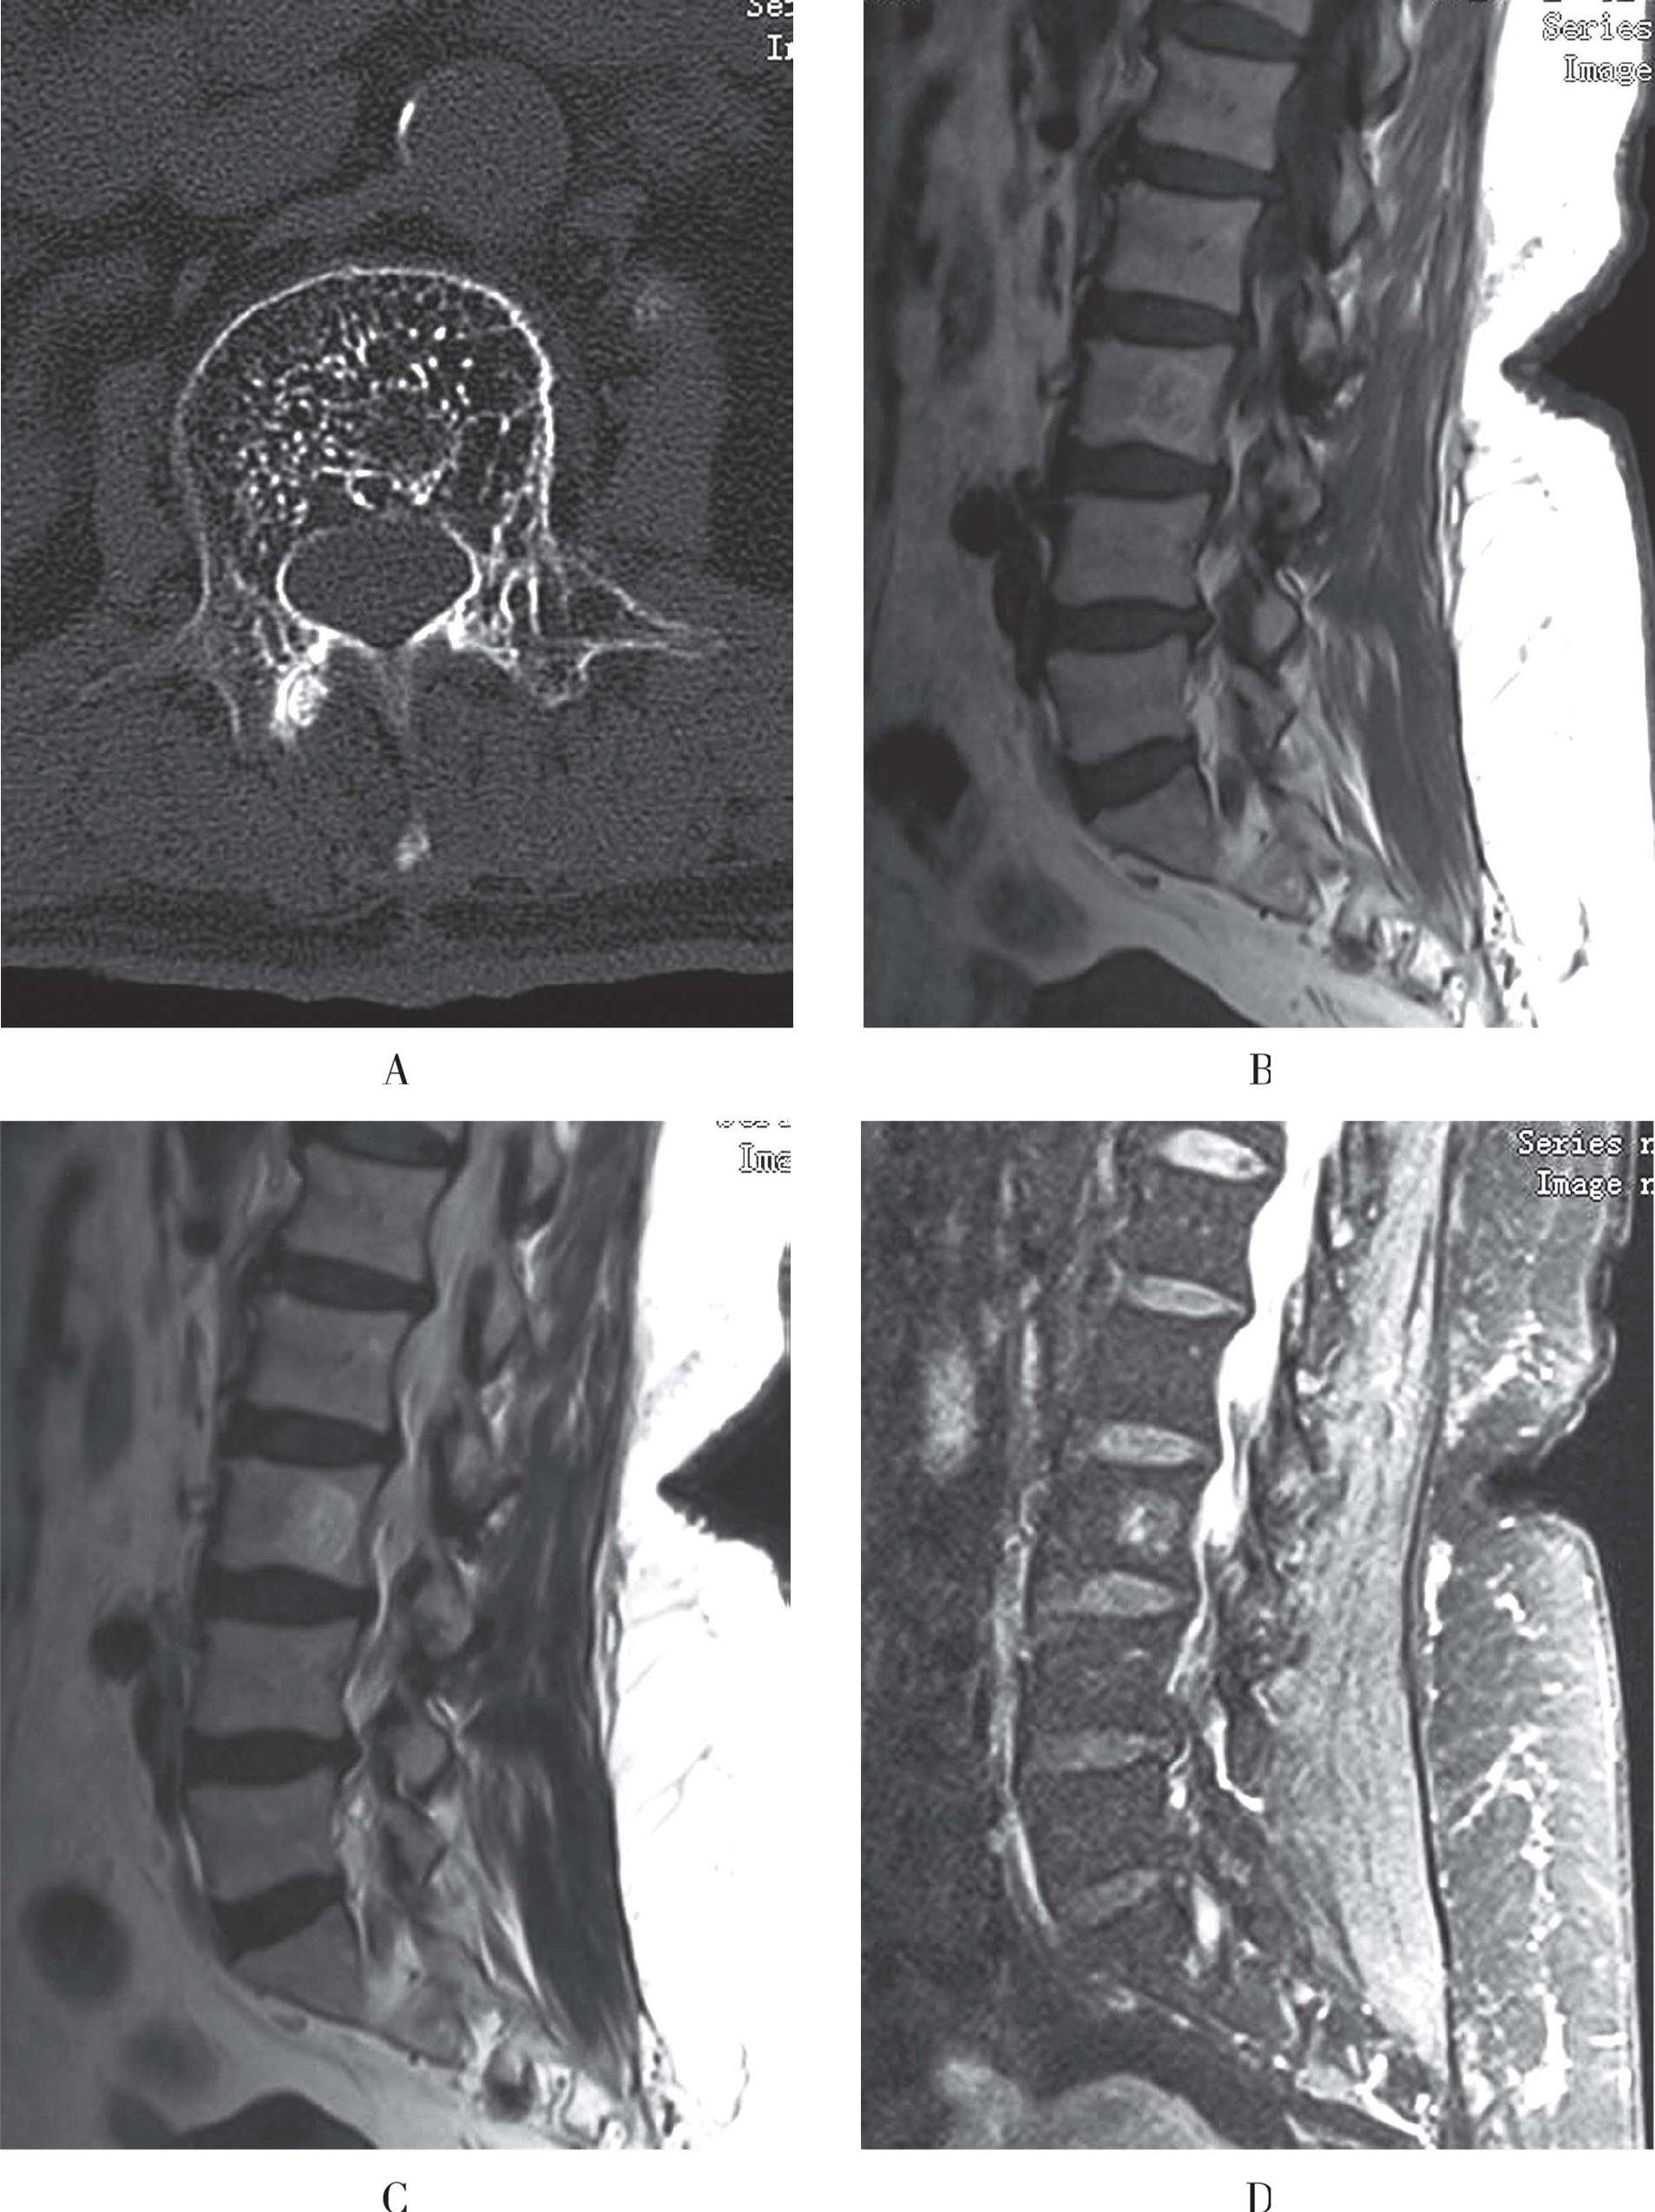

(1)X线表现为骶骨或斜坡的不对称膨胀性、溶骨性破坏,边界清晰,内有残留的骨片或小点状钙化,边缘可出现钙化,临近软组织内可见肿块,肿块内常有斑点状钙化。

(2)CT检查可清楚显示病变的范围及内部结构,瘤体表现为与周围肌肉相似的密度,增强后肿瘤均有强化,强化可均匀或不均匀(图3-53A)。

(3)MRI肿瘤在T1WI呈低至中等信号,T2WI呈高信号,其信号常较均匀。有些病灶因残留的骨片和钙化或为破坏的骶骨椎间盘而信号不均匀,T1WI及T2WI均表现为低信号,如有出血则为均匀高信号。MRI矢状面显示病变的范围及临近解剖关系最佳,肿块可向前推移直肠、膀胱和子宫。增强后肿块均匀强化(图3-53B至图3-53D)。

A、B. CT示骶骨溶骨性骨质破坏,临近见较大软组织肿块,增强后轻度强化;C、D. T1WI肿块呈等信号,T2WI肿块呈高信号

图3-53 脊索瘤的影像学表现